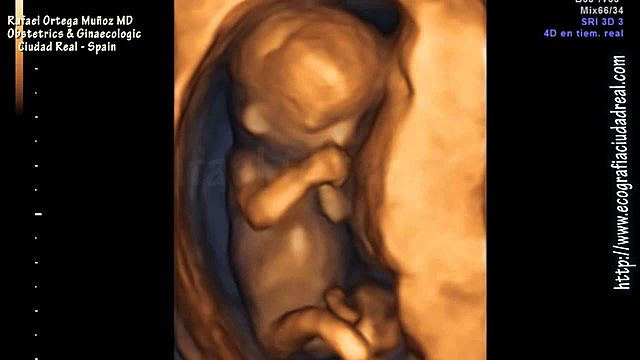

• Semana 29

29

Semana 29

-El cerebro crece rápidamente.

-El sistema nervioso se desarrolla lo suficiente para controlar algunas funciones del cuerpo.

-Los párpados del feto se pueden abrir y cerrar.

-El aparato respiratorio, aunque inmaduro, produce agente tensioactivo (esta sustancia ayuda a que los alvéolos se llenen de aire).